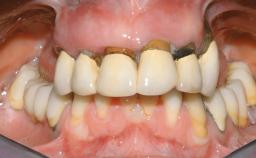

A 63-year-old male patient was referred for a consultation and treatment of partial edentulism in the maxilla. The patient presented with residual anterior teeth and declined a partial removable prosthesis. He reported that the maxillary posterior teeth had been extracted due to mobility and periodontal disease two months before the consultation. The patient’s chief complaint was that his residual maxillary teeth were mobile and that he was unable to chew. The patient’s desire was a stable and comfortable fixed maxillary rehabilitation. The patient was a light smoker (fewer than 10 cigarettes/ day), and his medical history was without significant findings. He was not on any regular medication at the time of consultation. The extraoral examination revealed a normal physiognomy with a correct distribution of the facial thirds. The patient presented a low lip line, and the transition line between teeth and soft tissues was not exposed during a forced smile.

Periodontal Status History of periodontitis or genetic predisposition